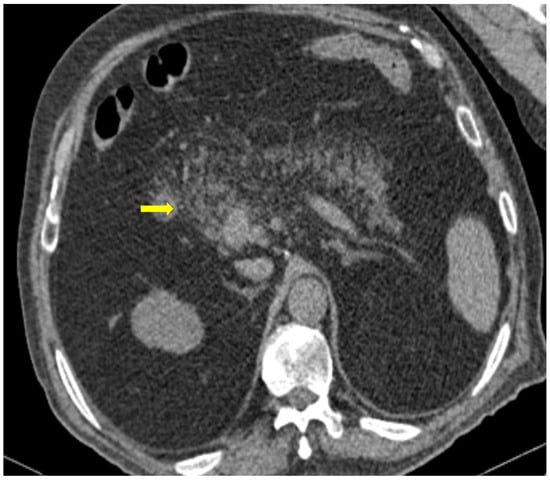

The temporal relationship between the onset of COVID-19 infection and inflammation of the pancreas has not been clearly established. Some patients develop COVID-19 symptoms and abdominal pain when the infection begins, whereas others present with AP several days after COVID-19 diagnosis (Figure 9) [37].

Figure 9. 81-year-old patient with COVID-19 pneumonia developed epigastric pain at the second day of hospitalization. CT demonstrating acute pancreatitis (yellow arrow).